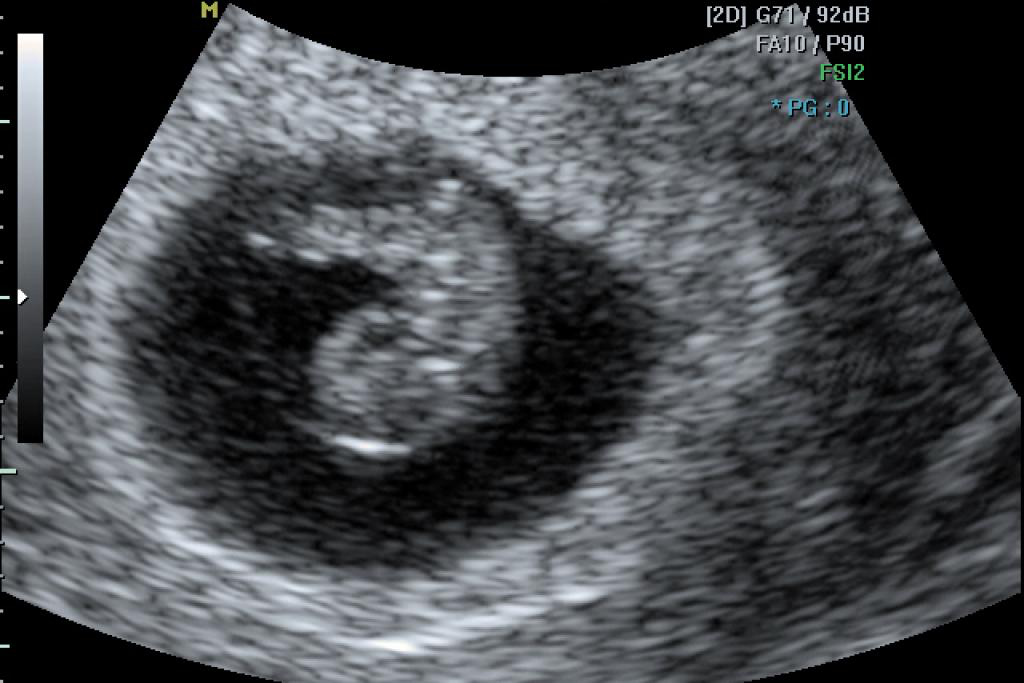

Haar klacht blijkt te zijn dat ze al drie maanden niet ongesteld is geweest en dat een zwangerschapstest tot haar grote teleurstelling negatief was. Bij oriënterend onderzoek is er geen reden voor een lichamelijke oorzaak van haar zwakte. Was het dan de teleurstelling van het niet-zwanger zijn? Of de ongerustheid van het uitblijven van de menstruatie?

Een bewijs van zwangerschap, dat is waar Zahra op gehoopt had.